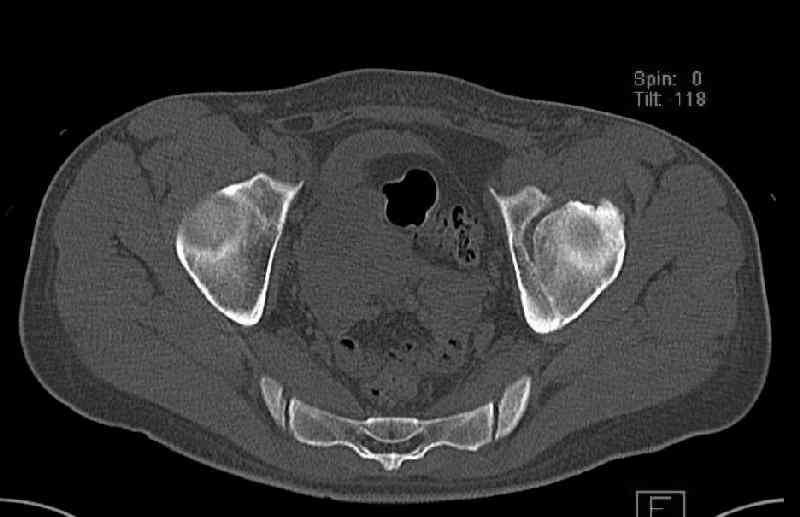

The last two images from the 3-D CT scan certainly makes the fracture look worse than the plan radiographs.

While not claiming to have the best 3D brain around, it appears to me from the limited images available, that the caudal segment is stable from the symphysis to the SI joint on the fracture side. I would love to see the rest of the transverse CT images to see where the fracture line actually exits posteriorly on both the inner and outer tables of the ilium. In my hands,

Some more images. Does it help to guess which part of the acetabulum is displaced?

Normal appearing SI joints and a healed posterior column limb... my bet's on caudal segment displacement.